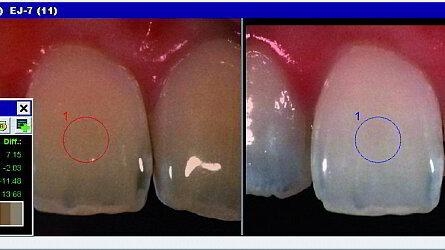

La De est la distance la plus courte dans l'espace chromatique du L*a*b* de la CIE entre les couleurs comparées et est déterminé en utilisant l'équation DE= (DL*2 + Da*2 + Db*2)1/2 où L* représente la légèreté, a* correspond à l'axe rouge-vert (la valeur positive indique le rouge, le négatif indique le vert), et le b* correspond à l'axe jaune-bleu (la valeur positive indique la valeur jaune et négative indique le bleu). Le changement de teinte, comme indiqué par le De, a été obtenu en recouvrant l'image de la même dent avant et après blanchiment de la dent (fig. 7), en utilisant le logiciel d'analyse Spectroshade (version 2.41).

Une augmentation de DE après blanchiment dentaire est habituellement attribuée à une augmentation en valeurs de L* et à une diminution en valeurs de b*. Il est intéressant de noter que les valeurs DE ont variées selon les dents, bien que toutes les dents aient été traitées avec la même concentration et la même durée d'exposition. Ceci suggère que chaque dent ait son propre degré de blanchiment, ce qui est un facteur très important qui influence l'efficacité du blanchiment dentaire.